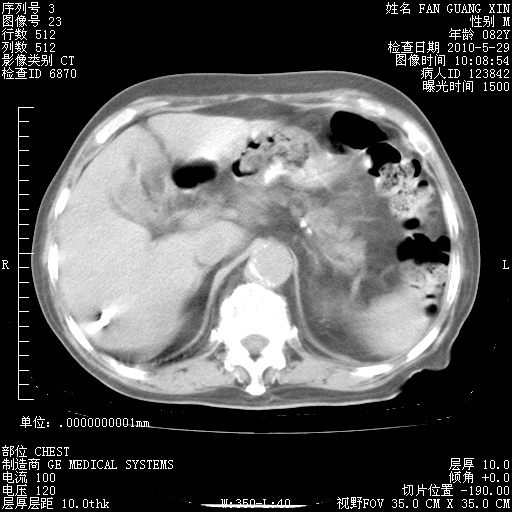

再治疗10天后的肺部CT 纵膈窗